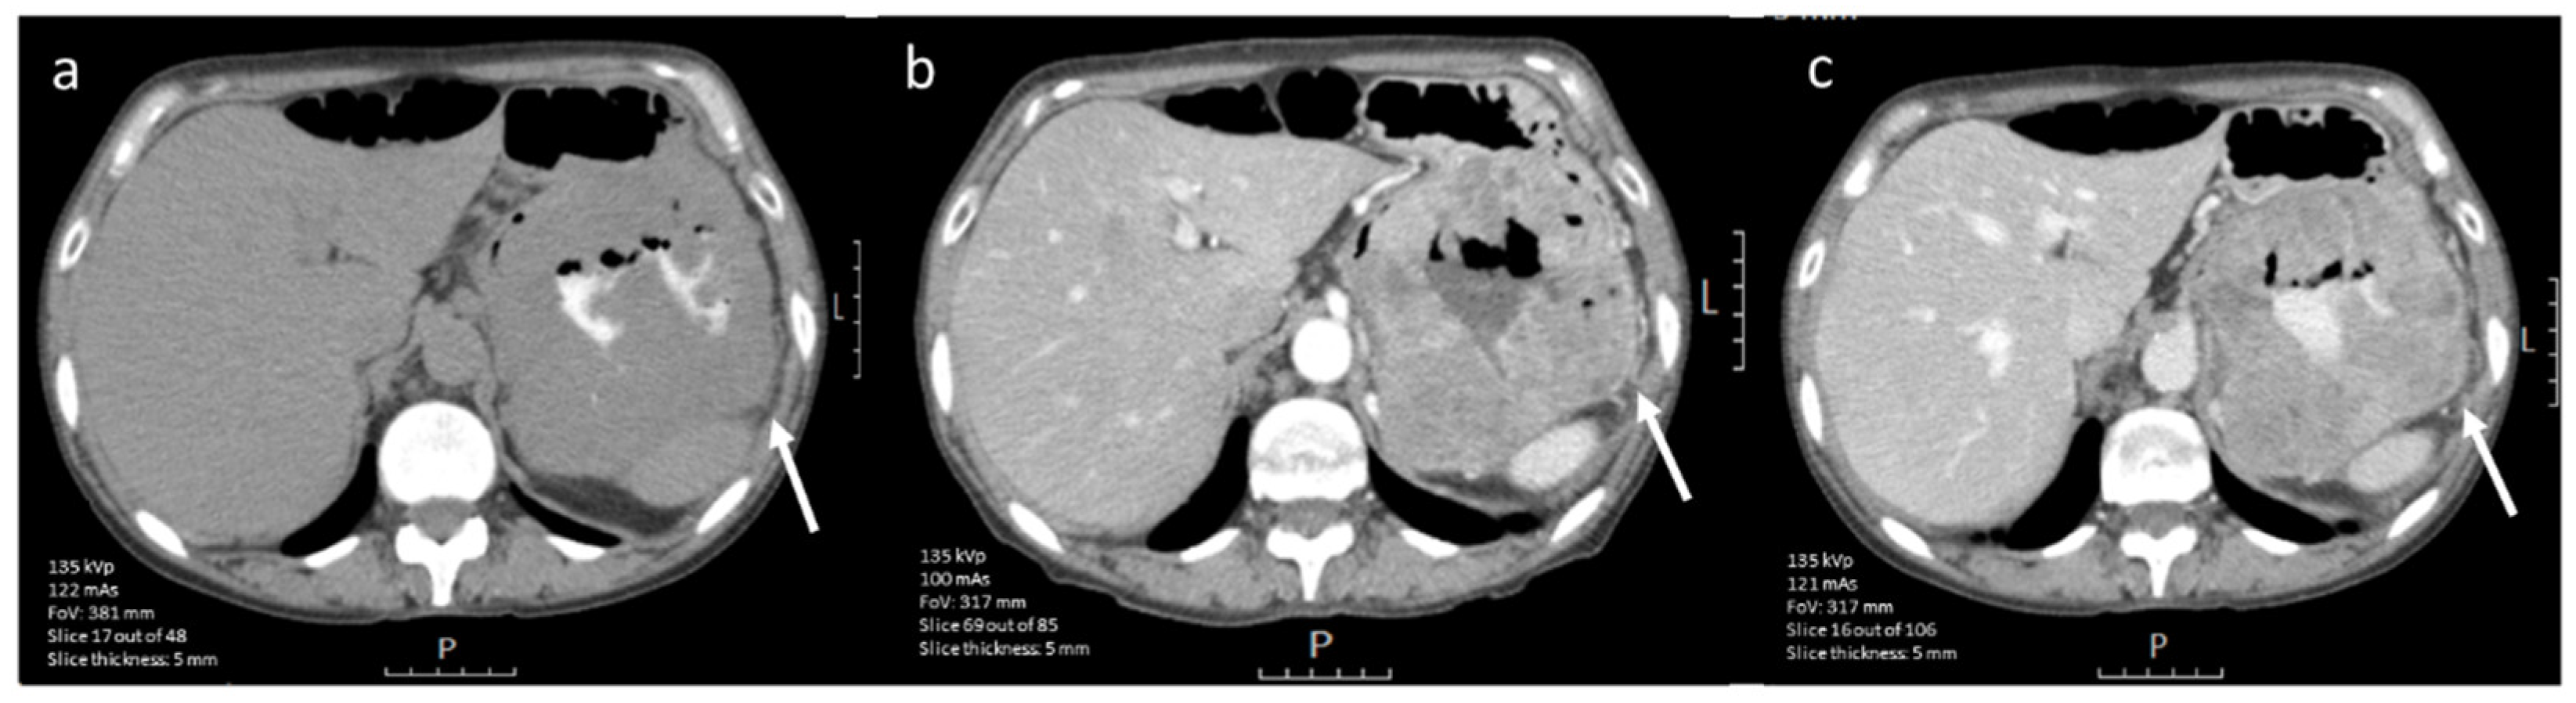

3.4.1. CE-CT Imaging